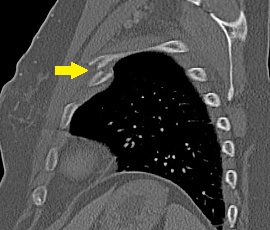

[肋骨骨折] 手術:肋骨骨折観血的手術

CT画像